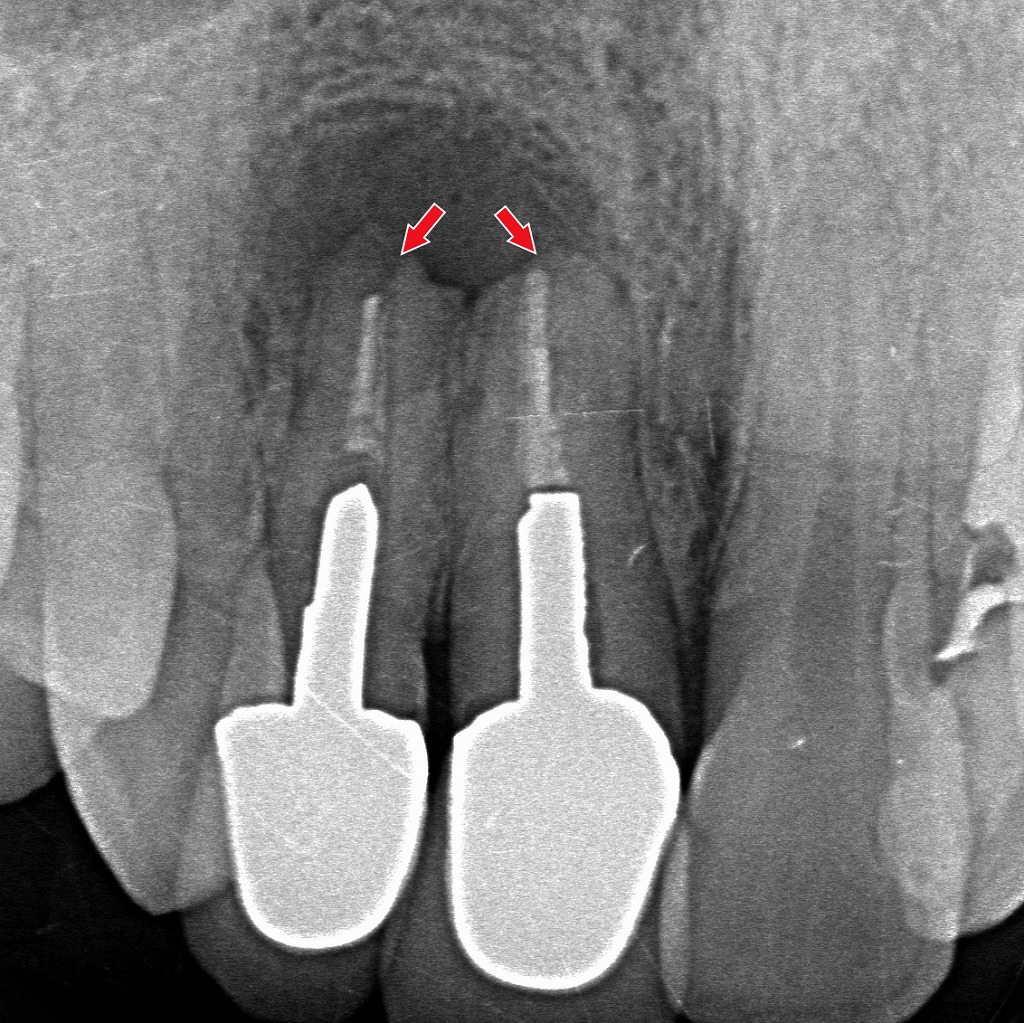

症例4:大人(永久歯)の過蓋咬合

この写真は、成人(永久歯)の過蓋咬合(かがいこうごう)を示す症例です。

補綴処置(被せ物・ブリッジ)後の口腔内で、咬み合わせが非常に深くなっていることがわかります。

🦷 過蓋咬合の特徴(この症例の所見)

- 上の前歯が下の前歯を過度に覆っており、下の歯がほとんど見えない

- 下の前歯は上顎前歯の裏側に深く入り込み、咬合が非常に深い(ディープバイト)

- 上の補綴歯(セラミック・クラウンなど)に歯肉には軽度の炎症・発赤があり、出血が見られる

深い噛み合わせ(過蓋咬合)では、上の前歯に過度な力が集中しやすく、歯根の先端部に慢性的なストレスが加わることで歯根吸収が進行することがあります。画像の赤矢印部分は、歯根が短く溶けている「外部吸収」が疑われる所見です。力のコントロールや早期の咬合改善が、さらなる吸収の予防につながります。